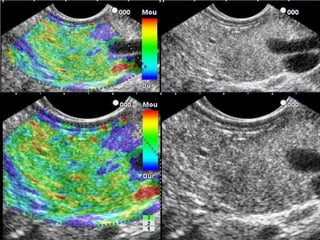

La elastografía es una técnica de imagen que permite detectar la deformidad del tejido al comprimirlo con un transductor ultrasónico. Mide la rigidez relativa de los tejidos y puede diferenciar tejidos blandos, inflamados o tumorales. Los principios involucran la correlación de alta velocidad y precisión de las imágenes ante la compresión para generar mapas de colores que representan el grado de deformidad. Estudios muestran que la elastografía ecoendoscópica es reproducible y puede diferenciar lesiones benignas